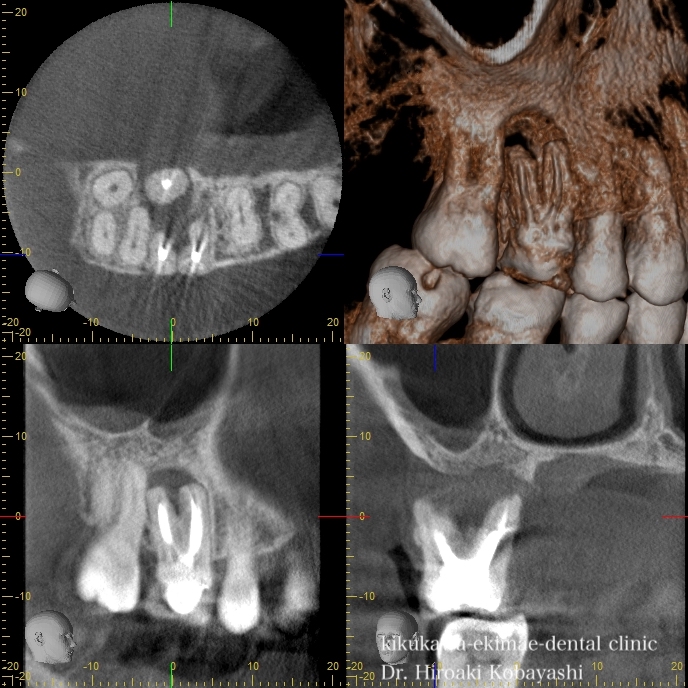

歯茎からオデキが出来たと来院されました。 CT撮影を行いますと、根の感染が見られました。感染の長期の放置により骨が溶けており、歯の保存が難しそうな状況でした。痛みもなく、特に生活に支障はありませんが、刻一刻と早期に歯を失う方向に進んでいます。おそらく、数年このままですと痛みもなくある日、ぐらぐらし、抜け落ちていたでしょう お話し合いの上、精密根管治療にて歯の保存を希望されましたので、治療を開始しました。   時間をかけ、顕微鏡を使用し感染の除去を行なっていきます。過去に根の処置を行なった時に入れたであろう薬剤や膿や出血が出てきます。 2時間程度のアポイントを3回お取りし、精密根管治療が完了しました。 オデキはなくなり、無事歯を残す事が出来ました。   CTにて経過を見ますと骨の再生が起きています 約6ヶ月〜程度かけて骨の再生が起こります。 リスク 極端に硬いものを噛むとかける可能性があります。 各種治療費はこちらから